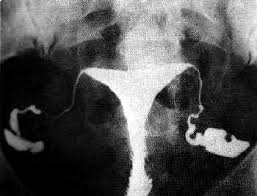

a. Pemeriksaan Hysterosalpingografi (HSG) adalah pemeriksaan X-ray dari tuba fallopii dan uterus dengan menggunakan kontras yang diinjeksikan melalui cervik uteri. Pada kasus infertilitas pemeriksaan ini bertujuan untuk mendiagnosa ada atau tidaknya sumbatan pada salah satu atau kedua tuba fallopii yang dapat menghambat penyatuan sperma dan sel telur.

b. HSG juga dapat memberikan gambaran dari cavum uteri dan mendeteksi adanya abnormalitas uterus yang juga dapat menyebabkan infertilitas atau keguguran yang berulang.

c. Kontras akan mengisi uterus dan tuba fallopii dan akhirnya akan tumpah memenuhi cavum pelvis disekeliling uterus dan tuba